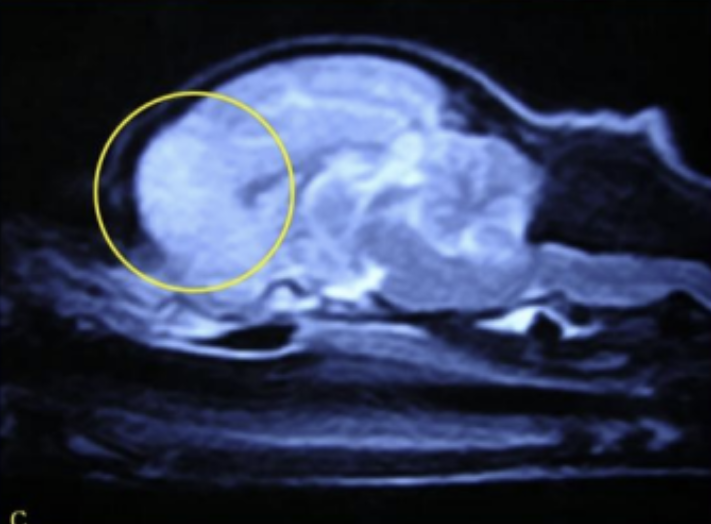

![]() Sagittal T2-weighted image of GME case | - frontal lobe์ solitaryํ๊ฒ ๋ํ๋ hyperintense lesion โ Focal GME |

![]() enhanced T1 & T2 weighted image | - ๋ ์์ชฝ๊น์ง multifocal lesions ์์ - ์ข ์๊ณผ ํท๊ฐ๋ฆฌ์ง ์๋๋ก ์ฃผ์. โ Multifocal GME |

![]() GME case | - ์ผ์ชฝ ๋์ ์ ๋ฐ์ ์ผ๋ก ์ฌํ ์ผ์ฆ ์๊ฒฌ - autopsy ๊ฒฐ๊ณผ, cerebral parenchyma์ swelling - ๋น๋์นญ์ ์ธ ์ธก๋์ค ๊ด์ฐฐ๋จ |

![]() NME (YT) | - T1 image์์๋ hyposignal (์ด๋ก๊ฒ ๋ณด์) - T2 image์์๋ hypersignal (๋ฐ๊ฒ ๋ณด์) โ NME ์ ํน์ง! * GME๋ T1์์ isoignal, T2์์ hypersignal |

![]() NME case | - ์ค๋ฅธ์ชฝ ๋์ temporal ์์ญ์ ๋ง์ ์ผ์ฆ ํ์ธ - ๋ถ๊ฒ ๊ฒฐ๊ณผ gray matter ์ผ๋ถ๊ฐ ์์ ํ ๊ดด์ฌ๋ ๊ฒ์ ํ์ธ |